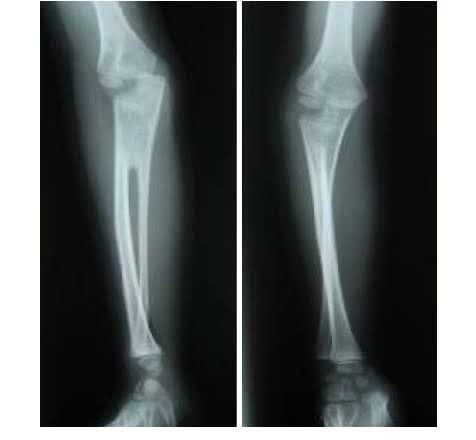

Radioulnar synostosis is a rare condition in which there is abnormal osseous union of radius and ulna. This condition can be congenital ( due to failure of segmentation) or post-traumatic synostosis (following trauma or injury). This leads to restricted movement in of forearm especially supination and pronation. Condition is treated by surgical intervention with high failure rates in post-traumatic conditions.